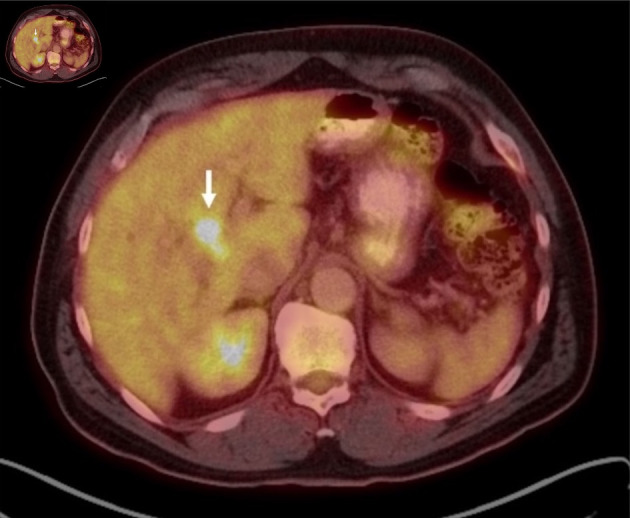

在极少数情况下,恶性胆道梗阻可能源于远处原发肿瘤转移到胆管。由于胆管转移瘤在临床和影像学上可能与胆管癌等原发性胆道肿瘤相似,因此这种现象往往给诊断带来挑战。我们介绍了一例独特的结直肠腺癌患者单发同步导管内胆管转移导致胆道梗阻的病例。患者最初被新诊断为肝曲处结肠癌,横断面影像学检查发现导管内肿块导致胆道梗阻。最初,导管内病变的性质并不确定,但通过组织病理学检查,最终确诊为转移性结直肠腺癌。该病例强调了区分转移性胆道梗阻和原发性胆道肿瘤的难度,并突出了在胆道肿块的非典型表现中考虑转移性疾病的重要性。我们讨论了有助于区分导管内结直肠腺癌转移瘤和原发性胆道肿瘤的几个关键放射学和组织病理学特征。

Malignant biliary obstruction can, in rare cases, arise from metastases to the biliary tree from distant primary tumors. This phenomenon often poses a diagnostic challenge, as bile duct metastases may clinically and radiologically mimic primary biliary tumors, such as cholangiocarcinoma. We present a unique case of solitary, synchronous intraductal biliary metastasis in a patient with colorectal adenocarcinoma that led to biliary obstruction. The patient initially presented with a new diagnosis of colon cancer at the hepatic flexure and was found, on cross-sectional imaging, to have biliary obstruction due to an intraductal mass. Initially, the nature of the intraductal lesion was uncertain; however, it was ultimately confirmed through histopathological examination to be metastatic colorectal adenocarcinoma. This case underscores the difficulty of distinguishing metastatic biliary obstruction from primary biliary tumors and highlights the importance of considering metastatic disease in atypical presentations of biliary masses. We discuss several key radiologic and histopathological features that may help differentiate intraductal colorectal adenocarcinoma metastases from primary biliary tumors.